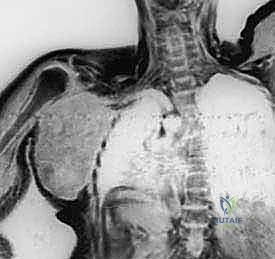

- التصوير الطبي المتقدم: استخدام الرنين المغناطيسي (MRI) لتقييم الأنسجة الرخوة، والأشعة المقطعية (CT scan) للصدر للبحث عن أي نقائل سرطانية (Metastasis)، والتصوير المقطعي بالإصدار البوزيتروني (PET Scan).